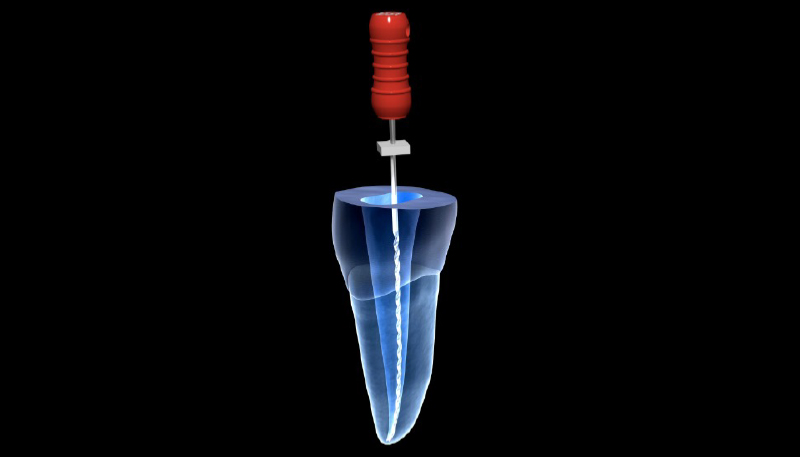

根管治療の具体的な治療とは

根管の中を薬が循環するように拡大して洗浄し、中の細菌を減らしてから根の中に菌が繁殖しないよう材料を詰める治療です。

歯の神経が残っている場合の治療方法

虫歯を全部取りきった後に歯をプラスチックの材料で補強します。 その後ラバーダムというゴムのマスクをつけて唾液などに含まれる菌が根管に入らないようにしてから根管治療を行います。

歯の神経が残っていない場合の治療方法

過去に根管治療がされている歯を治療する場合、被せ物と中の土台、古い材料を取り除いた後に根管治療をおこないます。

被せものや土台は削って外す為、再利用はできません。

2.ラバーダム(ゴムのマスク)

当院で行う根管治療では、ほとんどのケースで写真のようなゴムのマスク(ラバーダム)を装着しています。

このラバーダムには以下のメリットがあります。

- 無菌的治療が可能になる。

- 器具の落下防止

- 薬液の漏洩防止

- 粘膜の保護

無菌的治療が大切な理由

口腔内には細菌が数多く存在します。唾液や呼気にも細菌がいるため、ラバーダムをすることでそういった菌が治療している歯に侵入するのを防ぐ事が出来ます。

痛みを引き起こし、根管治療をしなくてはならなくなる原因は細菌です。

ラットを用いた実験では、歯の神経を無菌空間で露出させても痛みがでませんでした。

つまりこの細菌を出来る限り減らす事が、根管治療の目的になります。

実際、根管治療専門医のほとんどはこのラバーダムを行っています。

*ゴムアレルギーの方、鼻呼吸ができない方は使用できませんのでお申し出ください。